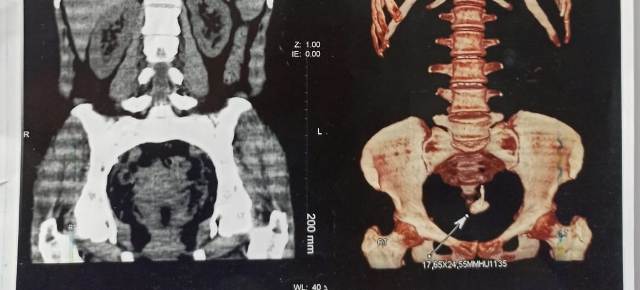

استخراج "لولب" من مثانة سيدة بمستشفى قنا الجامعي

وأضاف الدكتور جمال عبد الحميد الصغير رئيس قسم جراحة المسالك البولية بطب قنا والمستشفى الجامعي انه فور استقبال حالة مريضة في الأربعينيات من عمرها بالعيادة الخارجية التابعة للقسم تعاني من أعراض شديدة بالقناة البولية السفلى وتم عمل جميع الفحوصات الطبية والتي أظهرت وجود جسم غريب في منطقة المثانة البولية تسببت في تكوين عدد من الحصوات وتم عمل التدخل الجراحي للمريضة بواسطة منظار المثانة والرحم حيث تبين وجود لولب مهاجر قد تحرك من منطقة الرحم إلى المثانة البولية منذ حوالي 12 عاماً متسبباً في تكوين الحصوات والآلام المبرحة واضطرابات متكررة فى الدورة الشهرية.